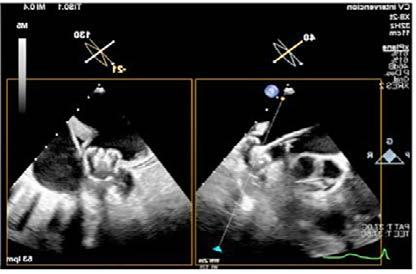

Mujer de 73 años con antecedentes de hipertensión arterial, trombopenia en contexto de lupus eritematoso sistémico, episodio de hipotiroidismo inducido por amiodarona y fibrilación auricular (FA) en estrategia de control de frecuencia cardiaca, anticoagulada con antivitamina K. Como fundamental antecedente cardiológicos destaca una valvulopatía reumática con afectación mitral, que inicialmente se reparó en 1997 mediante abordaje transapical (dejando como secuela aneurisma apical) y se recambió en 2007 por prótesis mecánica. Posteriormente, fue diagnosticada de doble lesión aórtica reumática con estenosis severa e insuficiencia ligera, con fracción de eyección preservada, pero insuficiencia tricuspídea severa e hipertensión pulmonar de predominio poscapilar. Ingresó programada para implante percutáneo de válvula aórtica (TAVI) vía transfemoral, con los principales condicionantes de bloqueo de rama derecha y altura límite de tronco coronario izquierdo (TCI), por lo que se administró clopidogrel 600 mg previamente al procedimiento.

Previo implante de marcapasos temporal yugular derecho se llevó a cabo el procedimiento. Durante la liberación de prótesis mediante inflado del balón, tuvo lugar la embolización supra-anular de la misma, dejando por un lado una insuficiencia aórtica severa y por otro lado ocluyendo parcialmente ambos troncos coronarios. Empleando doble acceso radial se enganchó la prótesis mediante un lazo y se desplazó hacia aorta ascendente, dejando hueco para la colocación de una segunda prótesis en situación correcta y evitando la oclusión de los ostium coronarios y troncos supra-aórticos. En ausencia de bloqueo auriculoventricular se retiró el marcapasos temporal, se evidenció un hematoma yugular derecho y, a través de analítica, se detectó anemización de 2,5 puntos. Mediante angiografía, se descartó enfermedad coronaria y, mediante ecocardiograma transesofágico, se confirmó normoposición de la prótesis, objetivándose al mismo tiempo una disección aórtica.

Se realizó una tomografía computarizada (TC) con contraste de forma emergente, que mostró una disección aórtica iatrogénica tipo A focal de origen en la zona 0 del cayado con extensión al tronco braquiocefálico derecho (1) sin afectar al resto de troncos supra-aórticos, cayado o aorta descendente (Figuras 1 y 2); además del hematoma

Figuras 1 y 2: Prótesis aórtica migrada y disección aórtica focal tipo A, de origen en la curvatura menor del arco aórtico (zona 0) hasta la bifurcación de la arteria braquiocefálica derecha; sin afectación de del resto de troncos supra-aórticos, del resto del cayado aórtico o de la aorta descendente.